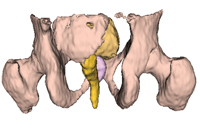

D: A surface rendering of the organs in the MRI “atlas” used to perform the automatic segmentation. |

Probabilistic atlas-based organ segmentation methods were developed to automatically segment the organs of interest (prostate, rectum, bladder, and femoral heads) from the MRI scans. After the scans were preprocessed (including correction of intensity inhomogeneity8 and patient movement artefacts9), the images and manually defined contours for each patient were combined into a single reference atlas by image registration methods. This atlas can then be warped onto the MRI scans of a new patient, automatically contouring the organs of interest (Box 3). A matching CT atlas enables the automatic estimation of electron densities from MRI scans by the same method.